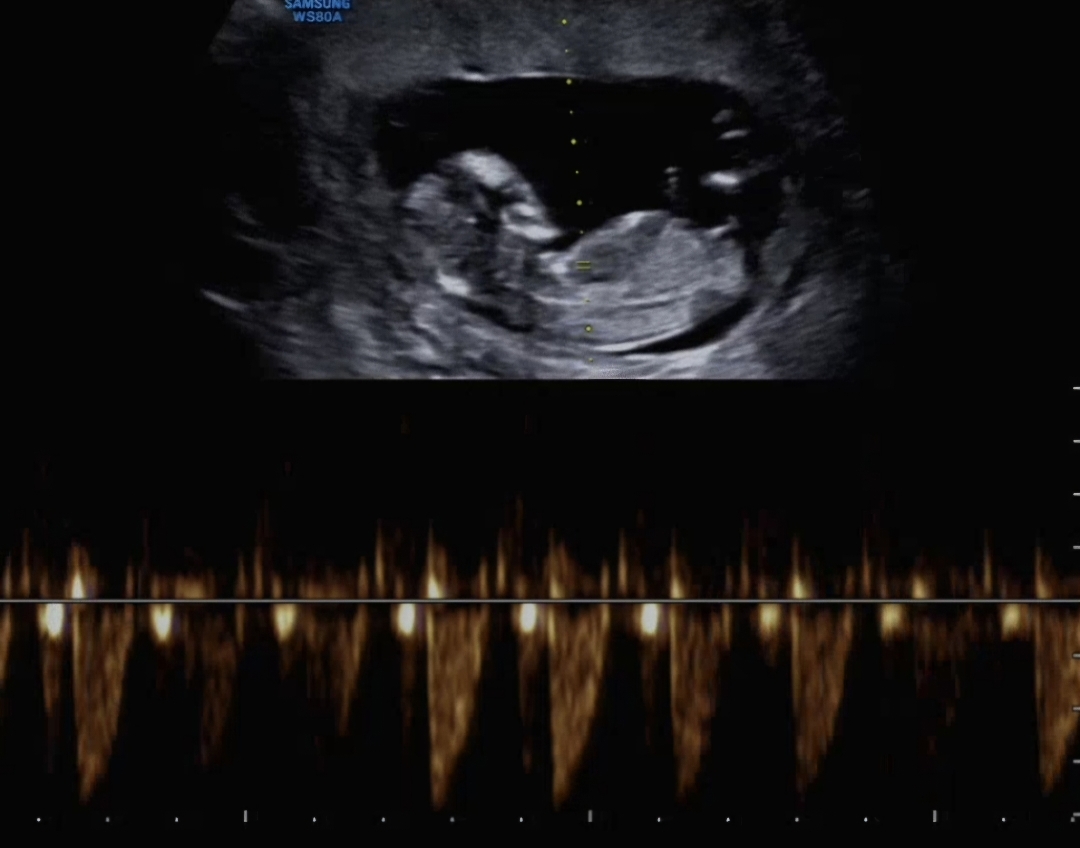

12주 배초음파 받고왔는데 각도법 봐주실 수 있나요~?!

안녕하세요! 12주 좀 지난 태아에요! 각도법 봐주실 수 있을까요~? 아들인지 딸인지 궁금하네요ㅠ.ㅠ

일케 애매했는데 딸이였어요